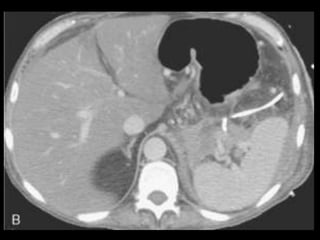

PANCREATITE AGUDA GRAVE

A administração de contraste IV é essencial,

especialmente em pacientes com PA grave, para

visualizar o pâncreas, diferenciar a glândula de

coleções líquidas adjacentes e do tecido

inflamatório peripancreático e demonstrar a

necrose pancreática.

Áreas focais ou difusas de realce diminuídas ou

ausente à TC contrastada dinâmica constituem

áreas de isquemia ou necrose.

TC tem precisão geral de 87% com S e E de 100%

para necrose extensa e 50% com áreas menores.